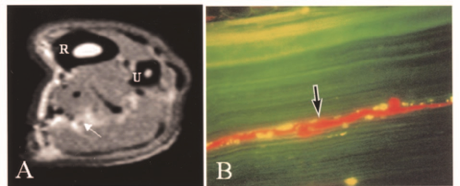

腕管松解术对双重挤压综合征和颈神经根病患者仍然有效

Hansen, LM, Jiang, EX, Hodson, NM, Livingston, N., Kazanjian, A., Wu, M., & Day, CS(2024)。有无双重挤压的患者...